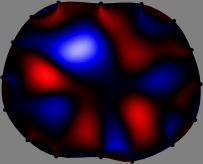

To explain the FER method, we closely examine the correlations among column vectors of the sensitivity matrix , described in Fig. 2. The correlation between and can be expressed as

for [23]. This shows that the column vector is like an EEG (electroencephalography) data induced by dipole sources with directions at locations . Given that two dipole sources at distant locations produce mutually independent data, the correlation between and decreases with the distance between and . Fig. 2 shows a few images of the correlation as a function of for four different positions . The correlation decreases rapidly as the distance increases. In the green regions where the correlation is almost zero, is nearly orthogonal to .

Fig. 2 shows that if and are far from each other, the corresponding columns of the sensitivity matrix are nearly orthogonal. This somewhat orthogonal structure of the sensitivity matrix motivates an algebraic formula that directly computes the local ensemble average of conductivity changes at each point using the inner product between changes in the data and a scaled sensitivity vector at that point: